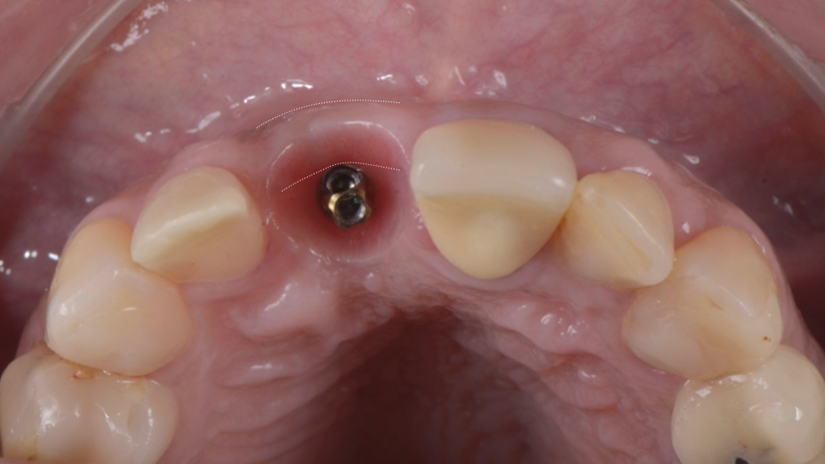

A região anterior da maxila é uma das áreas mais desafiadoras para reabilitação protética, principalmente quando se trata de implantes mal posicionados. Este caso clínico ilustra uma abordagem resolutiva para um implante vestibularizado na região do elemento 11, originalmente restaurado com um pilar reto tipo Smart de 4,5 mm, que inviabilizava a confecção de uma coroa parafusada esteticamente satisfatória.

A paciente apresentava queixas estéticas e funcionais. Após avaliação clínica e radiográfica, optou-se pela substituição do pilar reto por um pilar Ideale angulado de 17 graus e 3,3 mm de diâmetro. Esse componente mais estreito e angulado permitiu corrigir o eixo emergente da futura coroa, viabilizando o planejamento de uma prótese parafusada na região estética.

O caso foi conduzido com planejamento cuidadoso, moldagens analógicas e provas clínicas. A reabilitação foi finalizada com a instalação de uma coroa metalocerâmica parafusada, garantindo estética, funcionalidade e reversibilidade do conjunto protético.